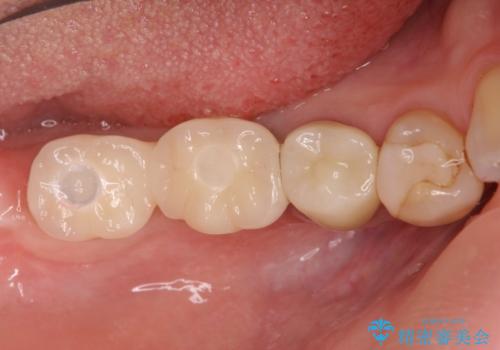

- 77万円(インプラント×2 アバットメント×2 ジルコニアクラウン×2 骨の造成)費用は治療当時の料金となります

今回はインプラント埋入時に固定が得られたので同時に骨の造成を行い治療を進めることができました。